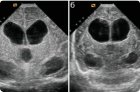

CT、またはX線CTは、脳構造の体内画像化の第1の方法である(英文文献では、この方法はしばしば「コンピュータ軸方向断層撮影法」と呼ばれる)。脳のコンピュータ断層撮影は、異なる(正常および変更された)脳組織におけるX線の吸収のわずかな差異を検出することを可能にする、結果のコンピュータ分析によるX線検査に基づいている。コンピュータグラフィックスを使用して、脳の「スライス」(3〜10mm厚)の層状画像が得られる。

脳のCTスキャンの精神障害の「有機」の方法で可視化萎縮性脳病変と一緒に精神科クリニックでは、統合失調症における構造異常や他のいくつかの「機能」とは、障害の機能の数を明らかにしました。例えば、統合失調症患者は、しばしば体積または部分的萎縮を増加させる、萎縮小脳及びより顕著な破壊前頭前皮質の存在が他の皮質領域に比べて、(「陰性」症状の存在および最悪効率神経弛緩薬治療と組み合わされる)拡張横方向および第三脳室を明らかにする脳梁、他の精神病患者と健常者で指摘されていない右半球の優位性と形態学的な脳の非対称性。

脳室(ventriculi脳腫瘍)、製造CSF(脳脊髄または脳脊髄液) - 両方の大脳半球では、間脳及び小脳及び延髄の間には、4つの特殊な空洞です。それらの病理学的拡大または拡大は、脳室肥大として定義される。